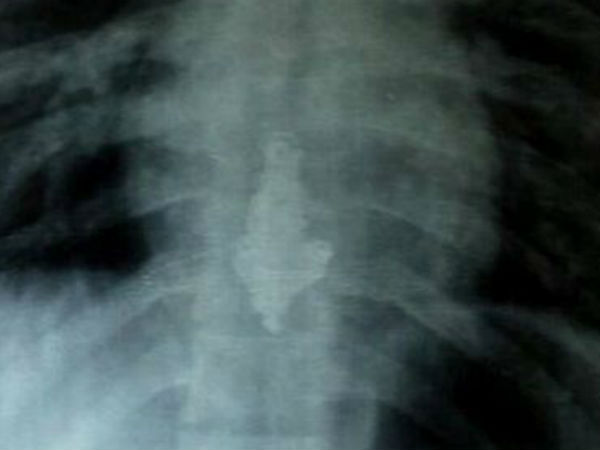

அவரை ரோந்து போலீசார் மற்றும் பொதுமக்கள் மடக்கி பிடித்தனர். ஆனால் அவரிடம் சோதனை செய்த போது நெக்லஸ் இல்லை. இதனால் சந்தேகம் அடைந்த போலீசார் அவரை சயான் மாநகராட்சி மருத்துவமனைக்கு அழைத்து சென்று எக்ஸ்ரே செய்து பார்த்தனர். அப்போது அவரது உணவு குழாயில் நெக்லஸ் சிக்கியிருப்பது தெரியவந்தது.

பின்னர், அடிவயிற்றில் இருந்து வெளியே வர முடியாதபடி நெக்லஸ் சிக்கி இருப்பது பரிசோதனையில் தெரியவந்தது. இதனால், அனில் யாதவிற்கு அறுவைச் சிகிச்சை செய்து நெக்லசை வெளியே எடுக்க மருத்துவர்கள் முடிவு செய்துள்ளனர்.